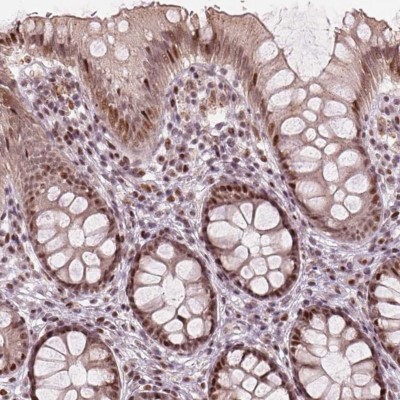

- Immunohistochemistry: TTC34 Antibody [NBP2-49495] - Staining of human colon shows moderate nuclear positivity in glandular cells.